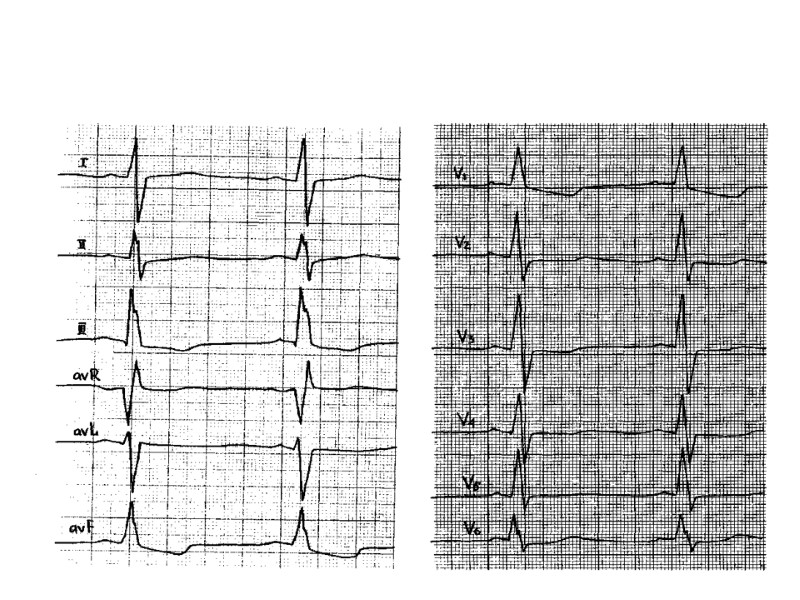

ВЭМ - исходно

ВЭМ- при нагрузке